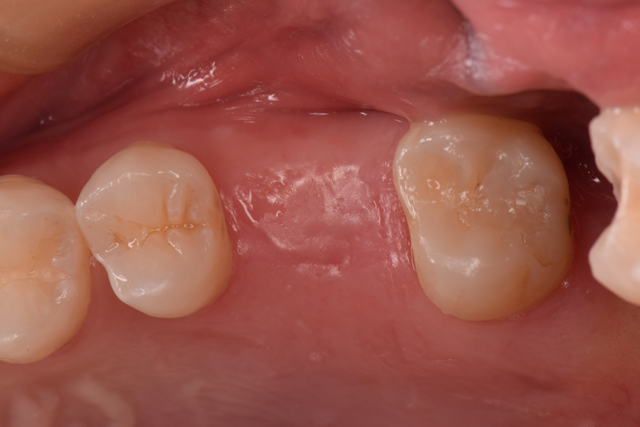

BEFORE

AFTER

| 年齢 | 31歳 女性 |

|---|---|

| 治療期間 | 4ヶ月間 |

| 治療内容 | インプラント手術 |

| 主訴 | インプラント治療を希望 |

| 治療費 | 495,000円 (税込) |

| リスク・副作用 | 上顎洞に近いため、穿孔の危険あり |